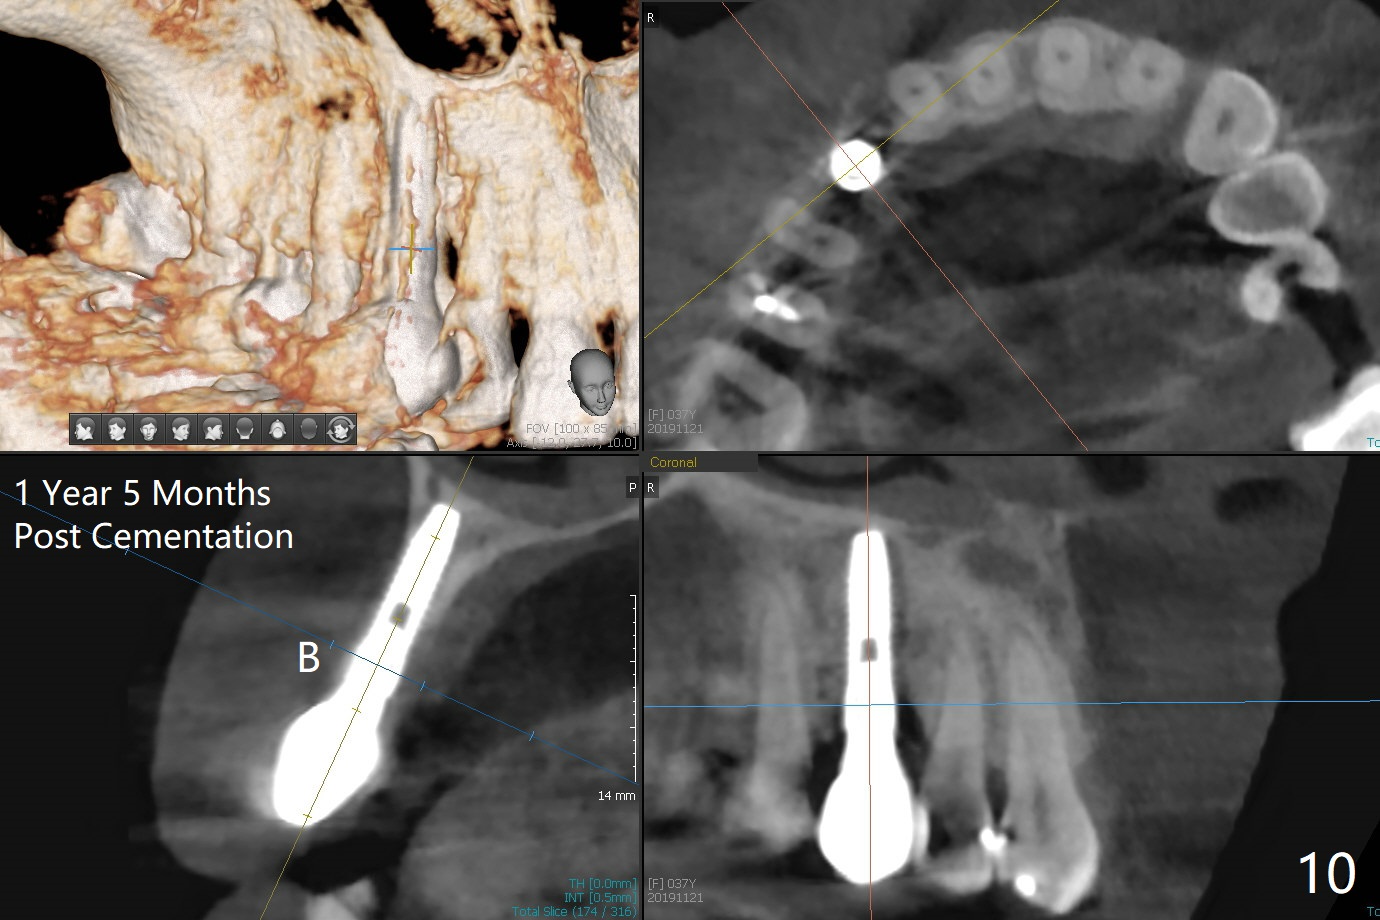

When the tooth #6 with loose crown and post (Fig.1) is extracted, there is no granulation tissue in the socket with the thin intact buccal plate. As planned, osteotomy is initiated in the mesio-palatal slope of the socket (Fig.2 red dashed line). After osteotomy for 3x20 mm (gingival level), a 3.8x15 mm dummy implant is placed partially (Fig.3 D). A final implant with the same dimension is placed with > 50 Ncm (Fig.4). Before and after placement of a 4.5x5(3) mm abutment, Vera graft is placed in the remaining socket space (mainly buccal, Fig.5 *). As routine, an immediate provisional is fabricated with occlusal clearance. The gingiva looks healthy around the provisional 1 week postop (Fig.6 P). Adjust and polish the mesioocclusal composite at #5 if necessary before impression. The bone graft appears to remain in place 4.5 months postop (Fig.7). A bevel buccal subgingival margin is placed prior to impression. The bone density around the coronal portion of the implant increases 9 months postop (4 months post cementation, Fig.8). There is no gingival erythema or edema around the implant crown at #6 ten months post cementation (Fig.6, as compared to preop condition and that of the neighboring crown (*)). Both the buccal and palatal plates are thin or absent 1 year 5 months post cementation (Fig.10,11, as compared to Fig.12 for the tooth #11 (thin buccal bone)). Socket shield should be done with a smaller implant.